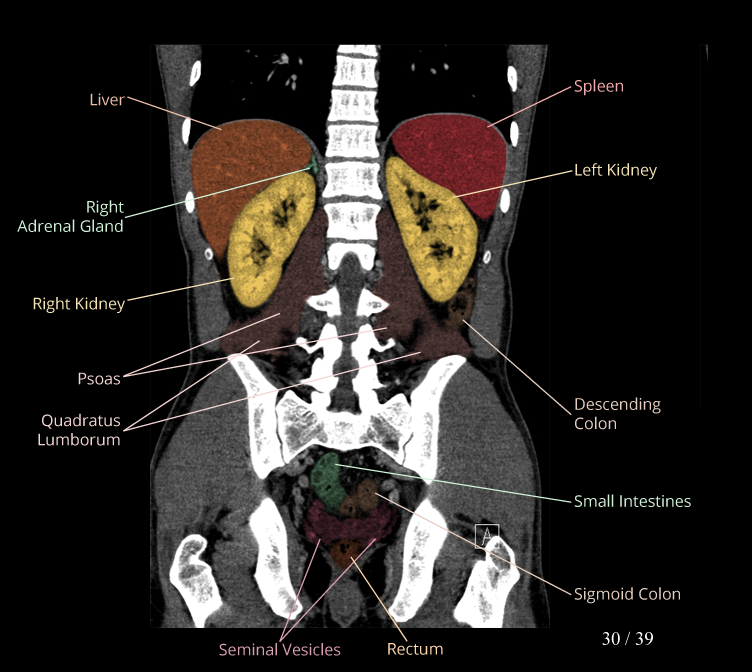

Body

Covers abdominal CT anatomy.